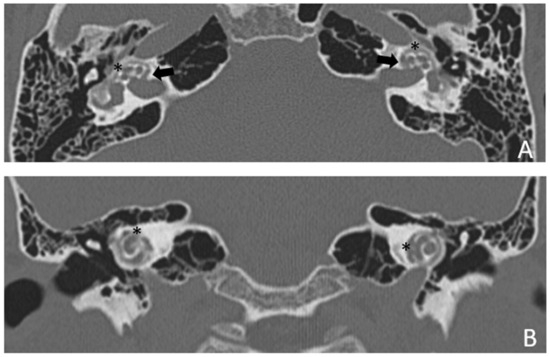

Within a few years, both ears showed a worsening of bone threshold to SNHL bilaterally. In 2017 (27 years since diagnosis) she developed profound SNHL with left-sided anacusis and underwent cochlear implantation in the left ear. CT and MR images showed a large cavity around the basal turn of the cochlea and massive osteorarefaction around the cochlea (‘double ring’ sign). The cavity appeared to contain cerebrospinal fluid but did not communicate with the cochlear lumen (Figure 1 and Figure 2).

Figure 1. CT images of patient #1 with osteogenesis Imperfecta. (A,B), right side in axial plane. (C,D), right side in coronal plane. (E,F), left side in axial plane. (G,H), left side in coronal plane. A pericochlear cavity is visible in all figures; arrows indicate its origin from the IAC. Asterisks indicate extension of osteorarefation into the cochlea.